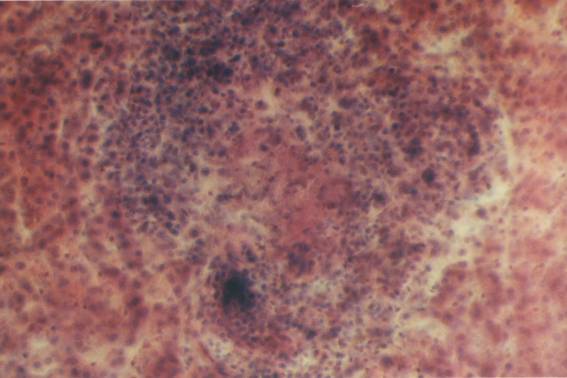

Під час дослідження гістопрепарату із селезінки спостерігали різке збільшення фолікулів, які поступово зливаються з навколишньою лейкозною тканиною. Червона пульпа заповнена лімфоїдними клітинами (рис. 5.2.9).

Рисунок 5.2.9 – Лімфоїдний лейкоз селезінки (40х7, гематоксилін-еозин)